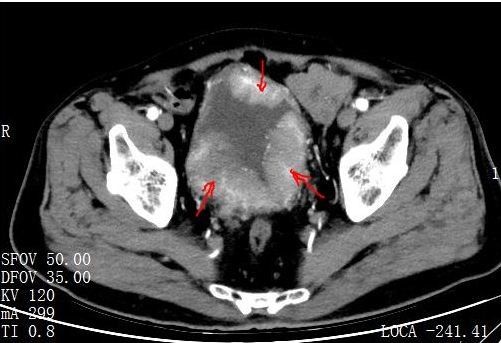

患者ct结果—箭头处为膀胱肿瘤

经过增强泌尿系ct,膀胱镜(活检)等检查,确诊为高级别尿路上皮癌,且